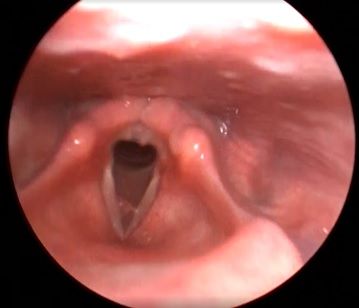

Рис 2А. Двусторонний паралич гортани. До операции.

Рис 2Б Двусторонний паралич гортани. 7 сутки после операции